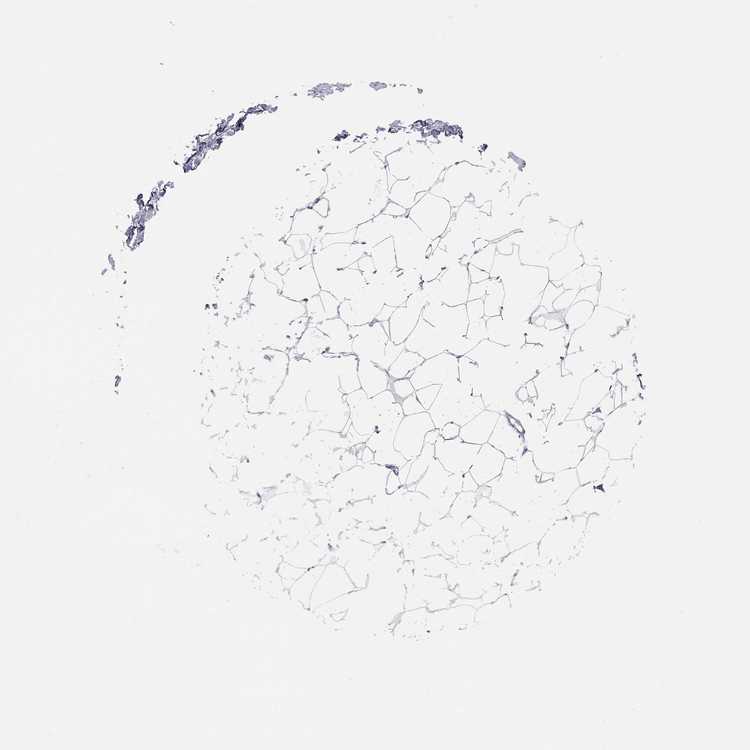

BREAST - Antibody stainingi

Antibody staining in the annotated cell types in the current human tissue is reported as not detected, low, medium, or high, based on conventional immunohistochemistry profiling in selected tissues. This score is based on the combination of the staining intensity and fraction of stained cells.

Each image is clickable and will lead to virtual microscopy that enables deeper exploration of all samples and also displays staining intensity scores, fraction scores and subcellular localization as well as patient and tissue information for each sample.

Antibody HPA078021

Adipocytes Not detected

Glandular cells Not detected

Myoepithelial cells Not detected